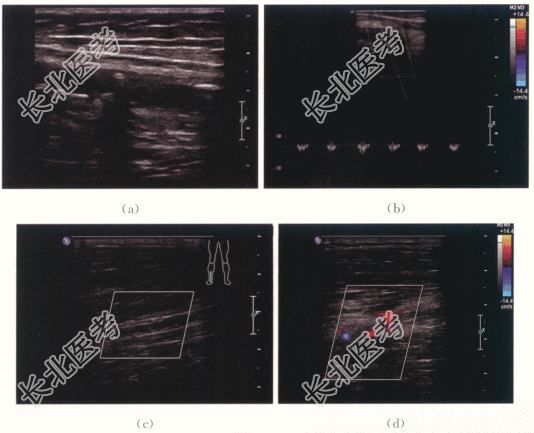

患者,男,67岁,因“5年前无明显诱因出现双下肢发凉怕冷”就诊,双足明显,未予重视。2年前步行时双下肢乏力,右侧明显,仍未系统治疗。半年前无诱因双足发凉怕冷明显加重,以右侧明显,步行约30~50m便被迫停止。

患者神清,气平。BP150mmHg/90mmHg。未见颈静脉怒张。双侧足背动脉搏动减弱。

TG2.9mmol/L,TC10.6mmol/L,HDL0.7mmol/L,LDL2.4mmol/L。

下肢动脉硬化性闭塞症。